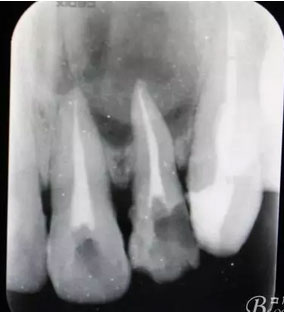

圖2.根管治療術(shù)中試尖影像

圖3.根管治療完成后的影像檢查: